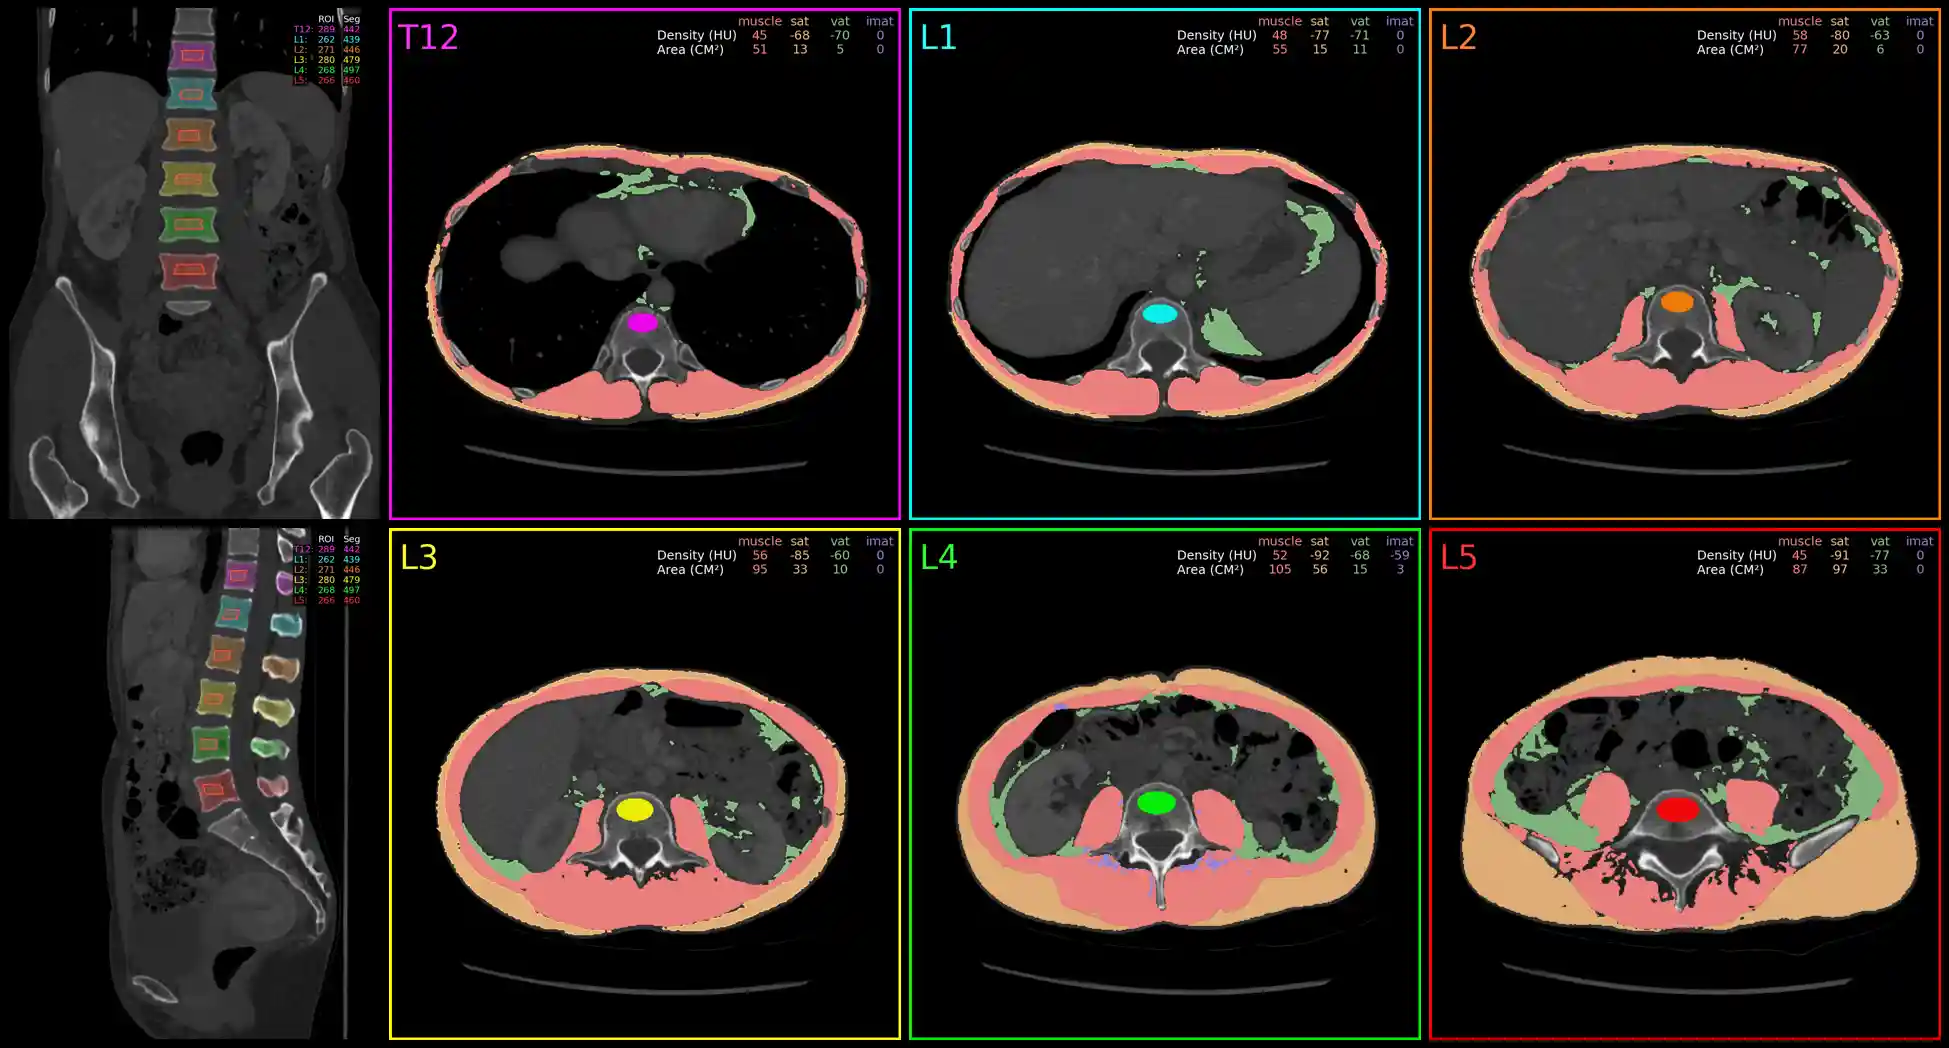

End-to-End Spine, Muscle, and Adipose Tissue Analysis at T12-L5

Example Output Image